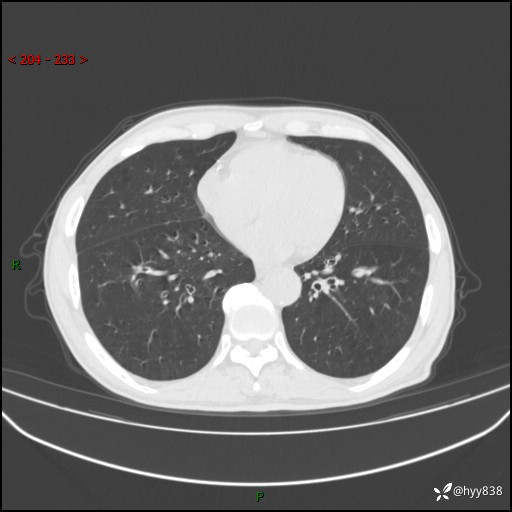

辅助检查:CT

胸部CT平扫

增强动脉期+静脉期

各期CT值:38Hu 52hu 55hu